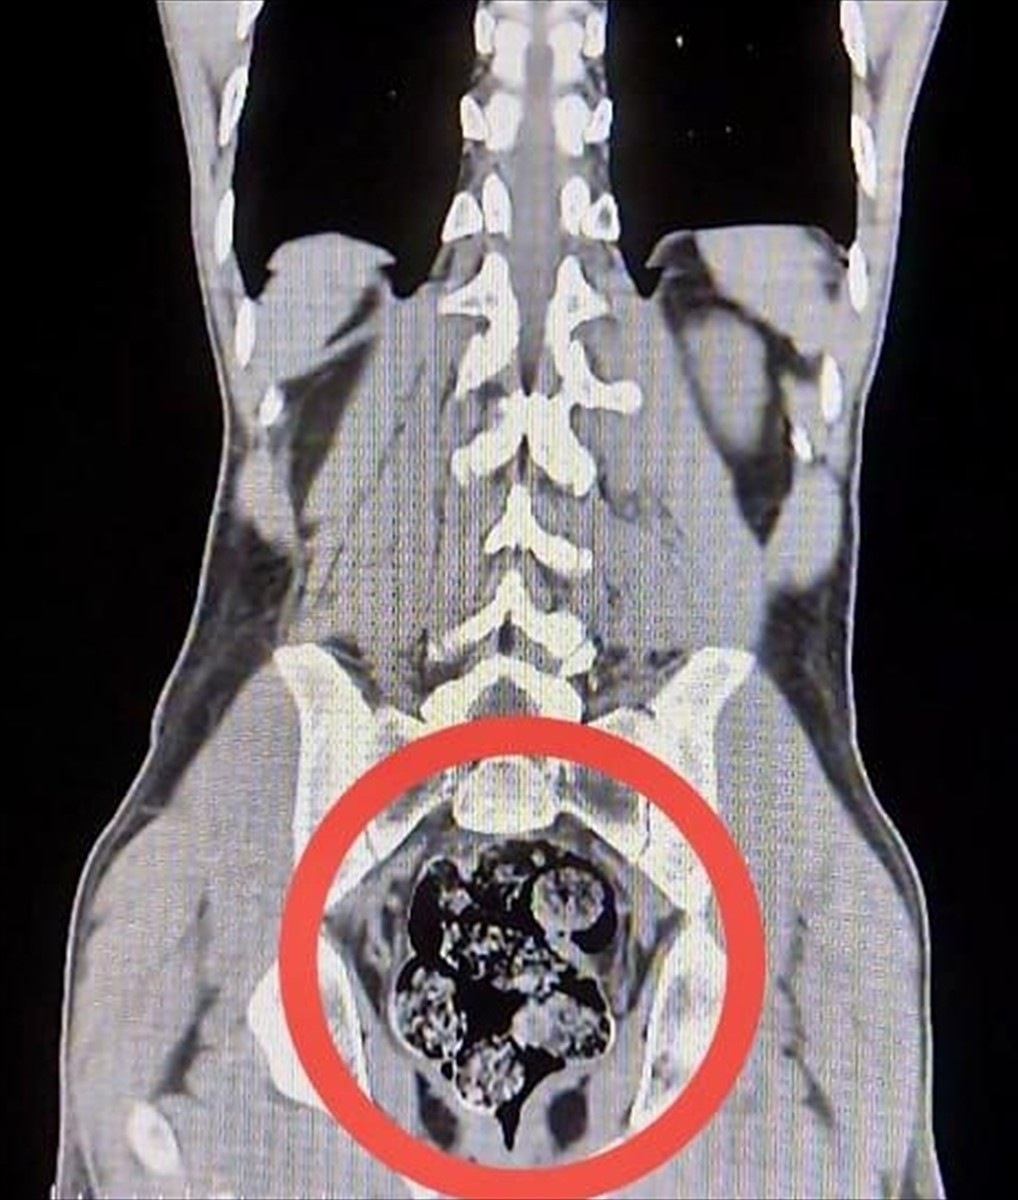

Yapılan operasyonda, Susuz ilçesinde yolcu otobüsünde gözaltına alınan zanlıların üstlerinde uyuşturucu madde bulunamadı. Ancak, sağlık kontrolü için Harakani Devlet Hastanesine sevk edilen Amır Rafıeı S.'nin mide ve bağırsaklarında 203,02 gram sentetik uyuşturucu madde tespit edildi. Bu madde, cerrahi müdahale ile çıkarıldı.